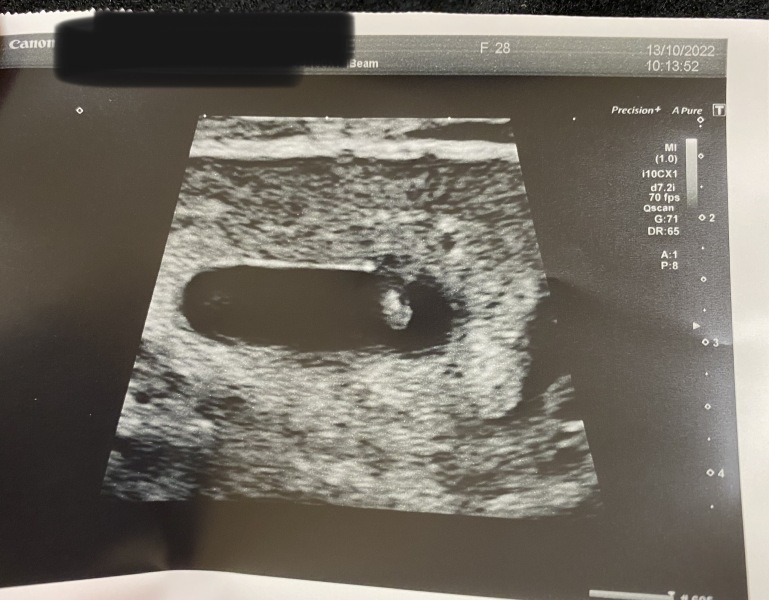

B1993 · 13/10/2022 10:54

Just a quick update from me though, after bleeding early on in this pregancy, I've had a scan and everything looks good! Baby measuring 5-6 weeks (I date myself at 6+1 today so hoping that'll be confirmed at 12 weeks). Even though it's so early and baby measured 4.2mm, I saw the heartbeat 💗 I'm over the moon!!

Are there any ramzi theory experts on here that could give me a prediction? (The scan was done abdominally, if that makes a difference?)